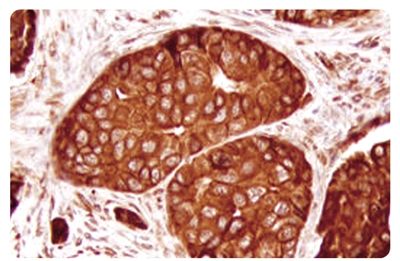

1990年,研究者发现了一种直接与遗传性乳腺癌有关的基因,命名为乳腺癌1号基因,英文简称BRCA1。早在2013年5月切除乳腺时,朱莉就称因携带遗传性BRCA1基因,她患卵巢癌的风险为50%,患乳腺癌的风险更高达87%。

中日医院乳腺、甲状腺外科(乳腺肿瘤中心主任)黄林平介绍,这种基因缺陷可能会导致乳腺癌、卵巢癌的发病。中国医学科学院肿瘤医院妇瘤科主治医师安菊生告诉记者,卵巢癌有散发与遗传之分,后者在5%-10%之间,另一方面,有家族病史的成员并非都会出现遗传性BRCA1基因突变,而BRCA基因缺陷人群中,约有60%-70%的人会出现遗传性卵巢癌。早在2013年切除乳腺时,朱莉就称因携带遗传性BRCA1基因,她患卵巢癌的风险为50%,患乳腺癌的风险更高达87%。也就是说,本身有家族病史,又携带遗传性基因,朱莉发生卵巢癌的几率会比正常人高出很多。

携带该基因就意味着癌症的可能吗?安菊生解释,朱莉的做法仅是针对个人情况做出的选择,她的预防性切除卵巢、输卵管的行为,在医学上是认可的,因为这将她本人患癌的几率大大降低。“但前提是一定要有相应的适应症,绝不是任何一个BRCA1基因突变的人都可以尝试的。”安菊生告诉记者,BRCA1基因突变并不意味着100%癌变,卵巢癌的发病与否是多种因素的综合作用过程,目前并未十分明确,具有一定的个体性。